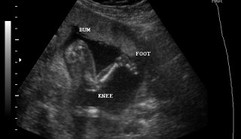

I'm 20 weeks and 4 days and it's our anomaly scan today. We found out na may Amniotic Band Syndrome si baby. Natunaw yung brain and left hand nya because of too much Amniotic fluid. Di naman cause of genetics and there was nothing to do to prevent it. Even tho na maipanganak ok sya di ko maiiuwi because ilang oras lang mabuhuhay ang baby girl ko. I'm so sad and mas malungkot si hubby iyak sya ng iyak. He knows na di ako umiiyak infront of others, but di ko mapigilan when he started crying. So we decided to terminate my pregnancy on Monday. She's kicking rn while I'm crying :(( We already picked out a name and we started buying stuff for her :(( Ive prayed every night na sana maging healthy ,normal and safe si baby but I dont know what i did wrong. We took extra precautions pa nga :( Nakakalungkot ng sobra. I just wanna share and ask if gano katagal kaya ako mabubuntis ulit? I feel like I NEED to be pregnant again, I NEED to hold my baby kasi di ko makakaya yung lungkot. Btw I'm 21 and my hubby is 24. Edit: I already terminated my pregnancy mga mamsh :( it was hard pero atleast my baby girl is dancing in heaven with her grandaddy, no more pain. Thank you for all your comments, nakakaiyak I'm okay now physically but emotionally hindi pa, I always cry every night when I pray. I miss my active baby and my baby bump. We decided to call her Leilani β‘ it's a Hawaiian name means heavenly flower. I also decided na mag vacation muna sa pinas, para mawala lungkot ko. It'll be sad and painful seeing my healthy baby nephews but they'll make me feel better. Labyu mga mamsh, thank you all for being with me on this painful journey.